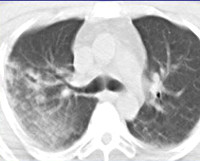

• Лучевые исследования. Рентгенография позволяет выявить участки инфильтрации легочной ткани через несколько дней после травмы. Она необходима при подозрении на перелом ребер, пневмо- и гемоторакс. Компьютерная томография рекомендуется при более тяжелых патологиях, таких как разрыв легкого, пневмоцеле и ателектазы.